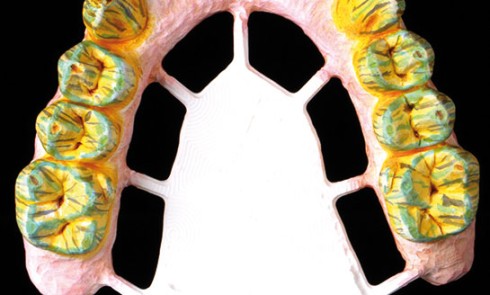

La pratique de la dentisterie numérique devient une part importante de l’activité de nombreux praticiens et laboratoires de prothèse (1)....La chaîne numérique en CFAO dentaire en prothèse conjointe

Nous vous proposons dans cet article de détailler pas à pas la réalisation au laboratoire d’une prothèse complète maxillaire implanto-portée,...Les implants courts au maxillaire postérieur : une alternative fiable et peu invasive